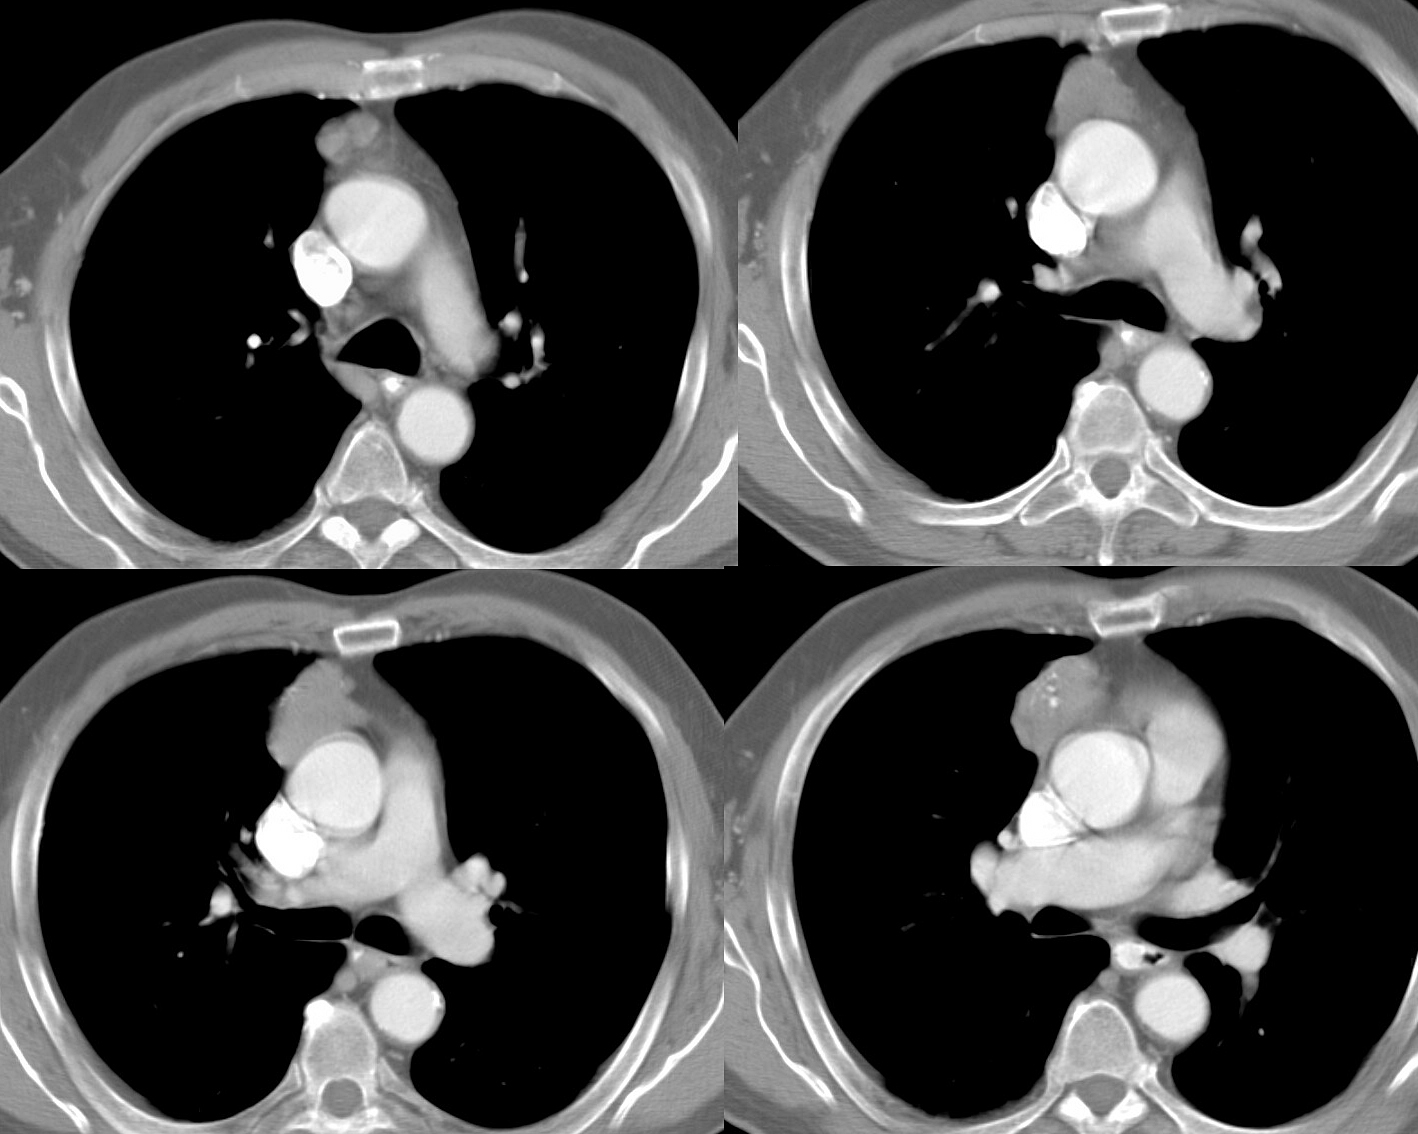

Case 2 Thymoma

Case 2

Thymoma